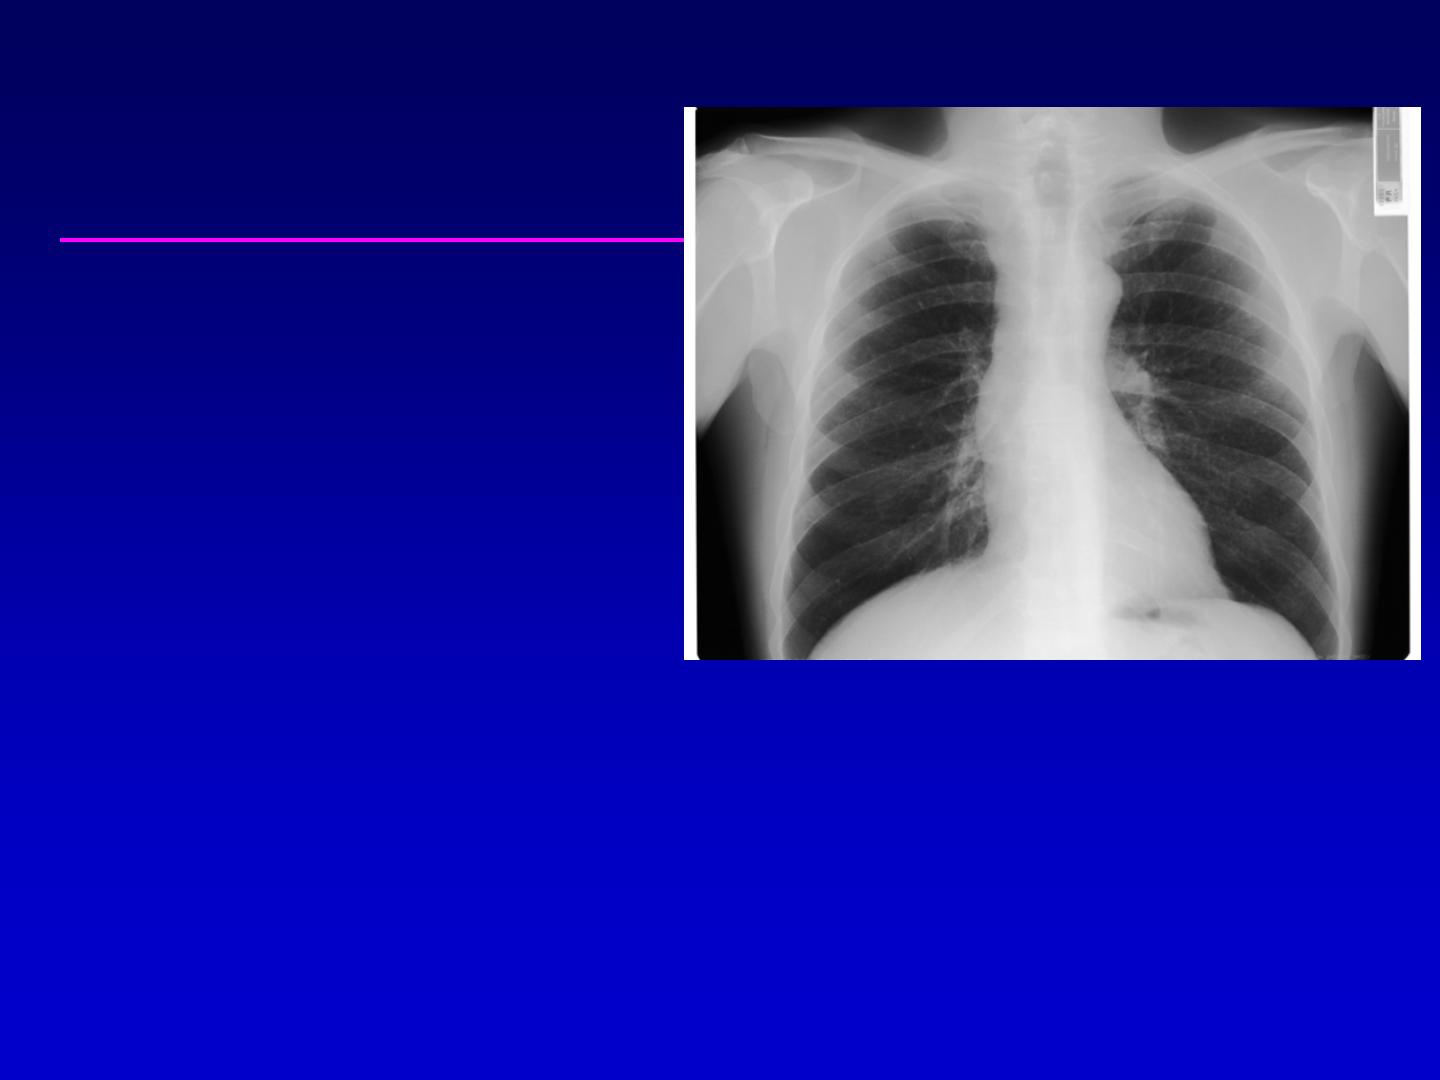

Radiographie thoracique :

élargissement médiastinal